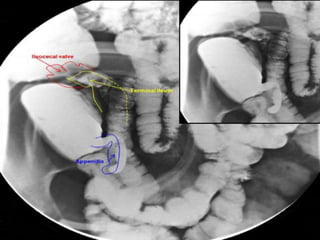

Fluoroscopy

• Dynamic radiography

–Permits real-time evaluation

of the gastrointestinal tract

– Barium Swallow (esophagus)

– Upper GI Series (stomach)

– Small Bowel Follow-through

– Barium Enema (colon)

• Barium (& air) is introduced

by enema or swallowing

•Barium appears white on the

images (high density

attenuates the x-ray beam)

•Can assess both intrinsic

(mucosal) and some extrinsic

(mass-effect) abnormalities.